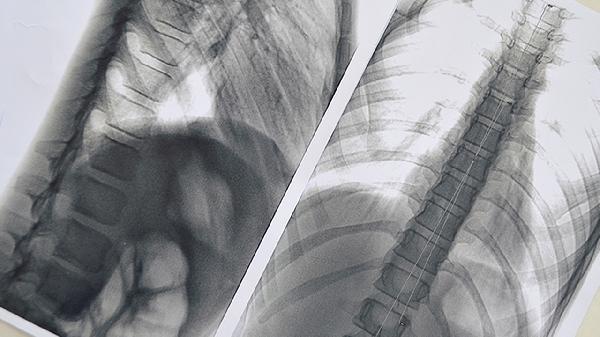

肺部有泡可能是由肺气肿、肺大泡或支气管扩张等疾病引起,需通过影像检查确诊并针对性治疗。原因可能与遗传、环境刺激、吸烟、感染等因素有关。治疗方法包括药物治疗、手术治疗和生活方式调整。